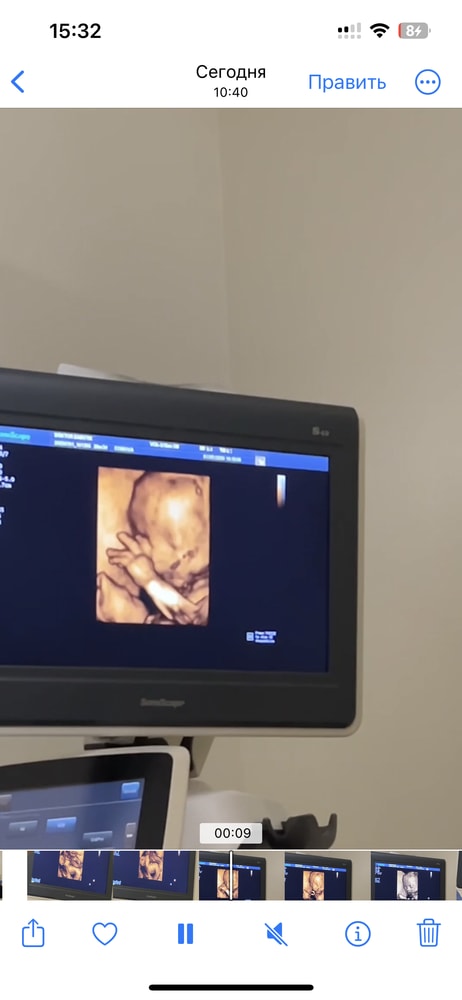

26+4 3д узи

УЗИ, КТГ, доплерСегодня были на 3д узи, это такие непередаваемые эмоции🥹

Он там и зевал, и лобик чесал. Весит уже 1кг